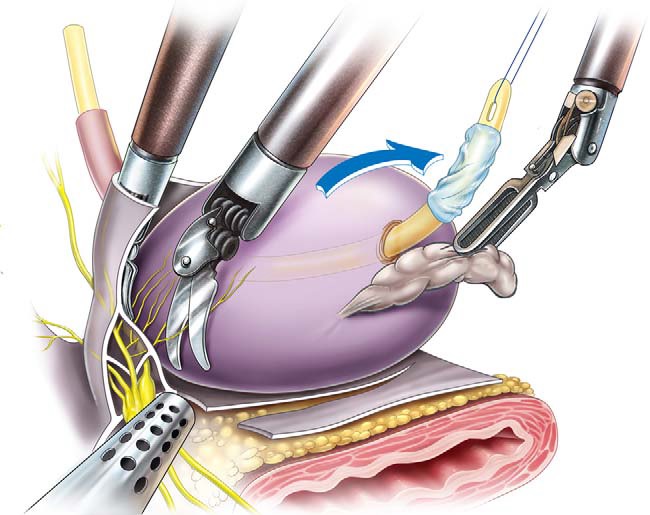

PROSTATECTOMIA ROBÓTICA

O tumor de próstata é o principal câncer que acomete ao homem, sendo de extrema importância o diagnóstico e tratamento precoces.

A PROSTATECTOMIA ROBÓTICA é uma técnica moderna e minimamente invasiva que utiliza uma plataforma robótica para melhorar a qualidade e precisão da cirurgia

NEFRECTOMIA ROBÓTICA

Cirurgia minimamente invasiva para tratamento de tumores renais malignos ou benignos.

Pode ser RADICAL, quando é retirado todo o rim ou PARCIAL, quando é retirado somente o tumor ficando o resto do rim saudável.